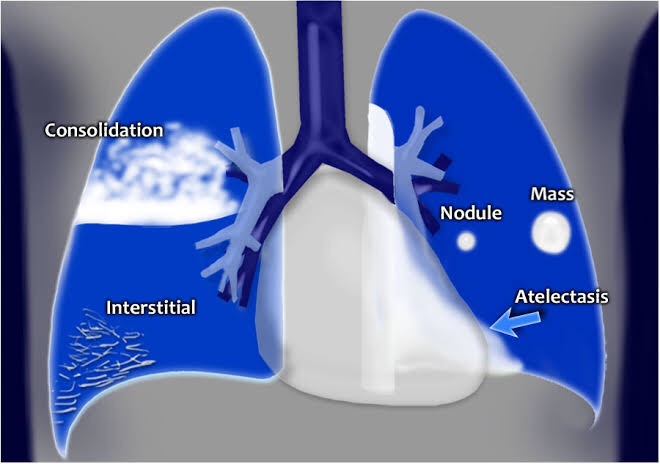

➡️ Pneumonia refers to infection within the lung and results in infective fluid and pus filling the alveolar spaces. This initially results in patchy airspace opacification and then more confluent consolidation.

➡️ Airspace opacification

- filling of the alveoli with infectious material and pus

- initially patchy

- becomes confluent as infection develops

➡️ Air bronchograms

- air-filled bronchi running through pus-filled alveoli